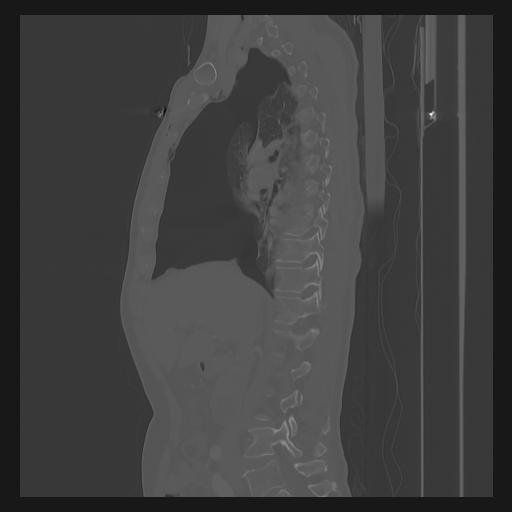

33 PULMON,CE,Sagittal,3.000,PULMON,Sagittal,